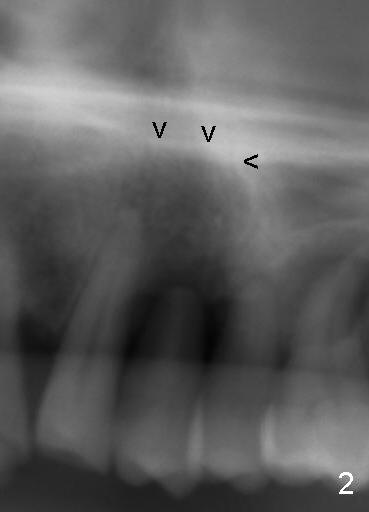

Dear Dr. Borgner: This Friday I may try D implant in a 50-year-old perio patient in #12 (Fig.1 *, Fig.2 is magnification of Fig.1 with sinus floor pointed by arrowheads), which was extracted ~ 1 month ago. PAs were taken yesterday (Fig.3). The socket must be partially empty. Can we start with RT2 or D1 spreader before using D2 one? #15 appears to be unnecessary. Tuesday, June 25, 2013 6:40 AM